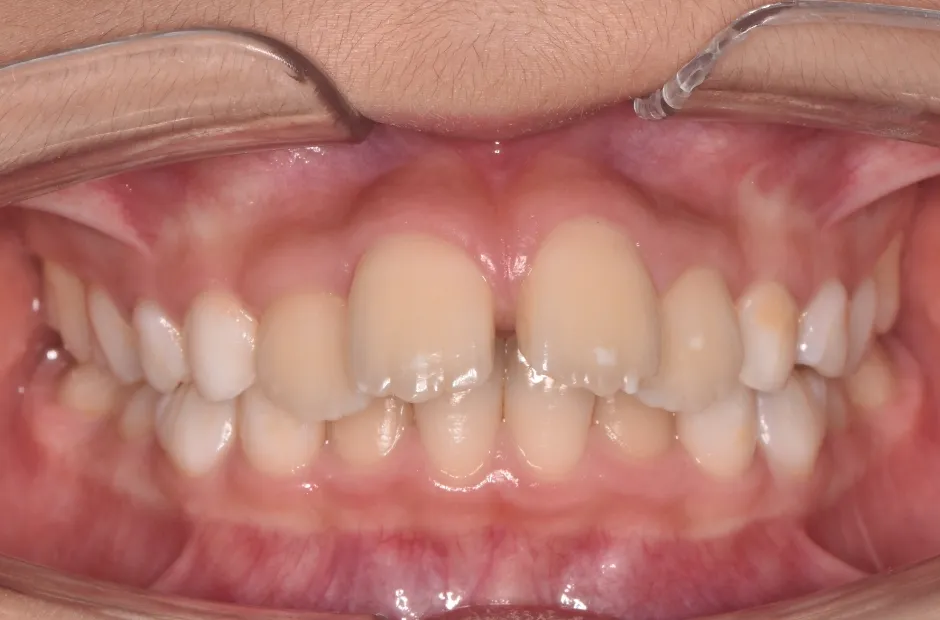

ブラケット矯正

前歯部反対咬合

| 診断名・主訴 | 前歯部反対咬合 |

|---|---|

| 年齢・性別 | 14歳・男性 |

| 治療期間・回数 | 1年2か月 |

| 治療に用いた主な装置 | ブラケット矯正 |

| 抜歯部位 | なし |

| 治療費 | 60万円(税抜) |

| リスク・副作用 | 装置による違和感・疼痛・歯肉退縮・歯根吸収・虫歯のリスクなど |

治療前

治療中

治療後